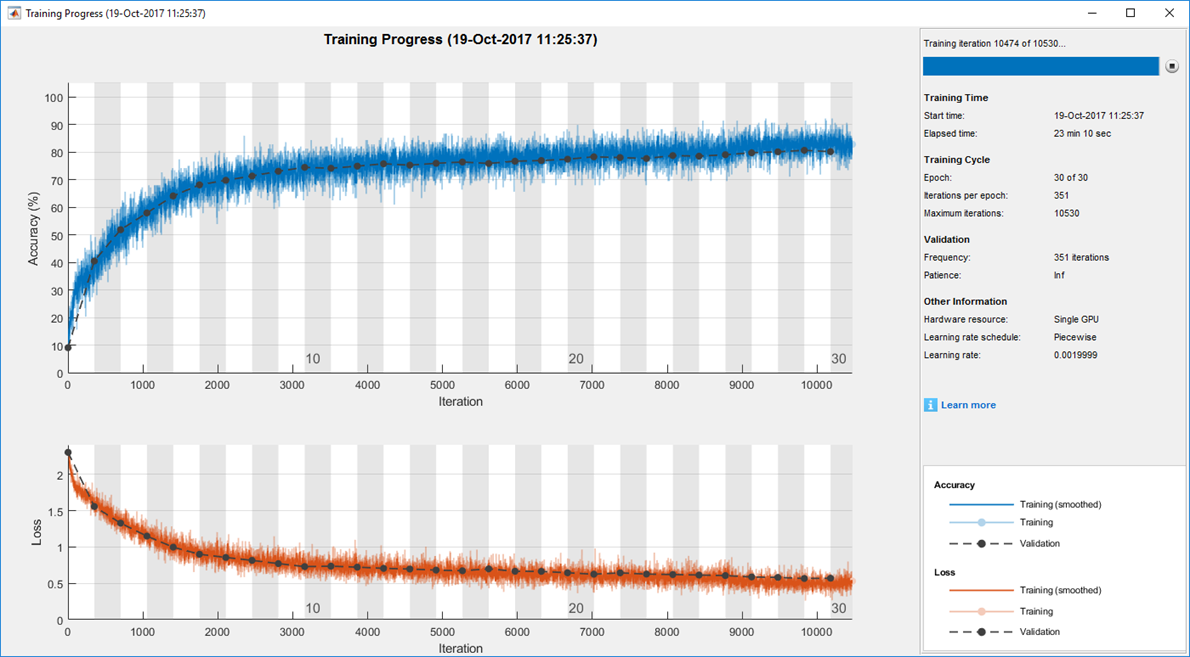

I based the initial structure of the CNN on the results of my earlier work on super-resolution. In that study, I found that a local region of 7 x 7 worked best, and I began with that size local region for my deep learning model. I subsequently experimented with local region sizes between 5 x 5 and 128 x 128, checking the clarity of the results each produced, before settling on 32 x 32 for lung area and 64 x 64 for non-lung area. Working in MATLAB, I also evaluated about 128 different CNN variants, trying different input sizes and filters as well as various numbers of convolutional layers. Training and Validating the CNNsUsing cross-validation, I trained the model with images from 11 patients and tested it with images from the one remaining patient. I repeated these steps 12 times with different training sets and test images. To accelerate this process, I trained in parallel on multiple NVIDIA® GeForce series GPUs using Parallel Computing Toolbox™. To monitor training progress, I plotted accuracy and loss using the monitoring visualization option in Deep Learning Toolbox™ (Figure 3).

Figure 3. Sample plot of training progress, generated with Deep Learning Toolbox. The results for each ultra-low-dose test image were evaluated against its corresponding normal-dose image using root-mean-square (RMS) levels and the structural similarity index (SSIM) for measuring image quality metrics. Next StepsPlans are in place to use my CNN-based system in an actual clinical setting. I am also exploring ways to deploy the system to a picture archiving and communication (PAC) server, which provides convenient storage of, and access to, medical images. One of the many advantages of developing medical imaging software in MATLAB is that the environment makes it easy to create an interface to the underlying algorithms and then distribute the entire package to doctors, a process that I have already completed for other MATLAB based systems that I’ve created. Ritsumeikan University is among the more than 1000 universities worldwide that provide campus-wide access to MATLAB and Simulink. With the Total Academic Headcount (TAH) License, researchers, faculty, and students have access to a common configuration of products, at the latest release level, for use anywhere—in the classroom, at home, in the lab, or in the field.